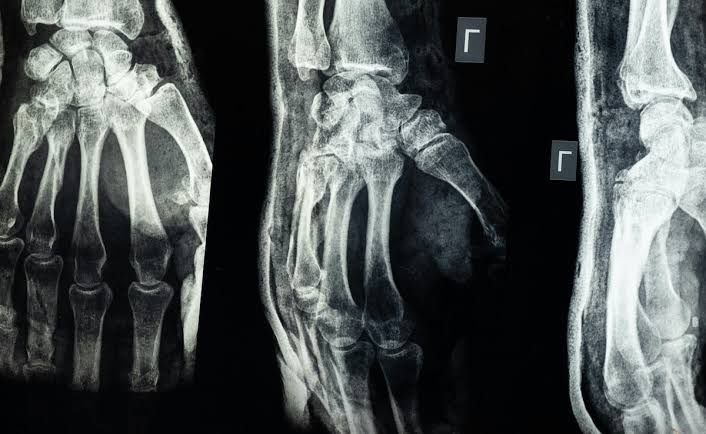

In a huge medical breakthrough, scientists in China have reportedly invented a bone glue that sets within three minutes and can heal fractures. The project, known as "Bone-02," was unveiled to the public by researchers in China's Zhejiang Province on September 10, according to NDTV, citing local reports.

The adhesive, meant for orthopedic use, could transform fracture and shattered bone care. Scientists have long sought an adhesive strong enough to secure such a bond that would also be safe and biocompatible. Many previous attempts failed due to toxicity or rejection by the body.

Bone-02 can establish solid attachment in 2 to 3 minutes, even in environments with heavy bleeding, said Lin. The glue is also slowly absorbed as the bone heals, negating the need for another surgery to take out implants, such as metal plates and screws.

Laboratory and clinical tests of this bone glue show promising results.Bone-02 has already been used to treat more than 150 patients, according to state news outlets. Surgery that typically calls for large incisions and metallic implants is over in less than three minutes with the glue.

The adhesive itself is also quite strong. They reported a bonding strength of more than 400 lb, shear strength of 0.5 MPa, and compressive strength of 10 MPa. These figures suggest that Bone-02 could potentially replace traditional metal implants, reducing the risks of infections and complications.